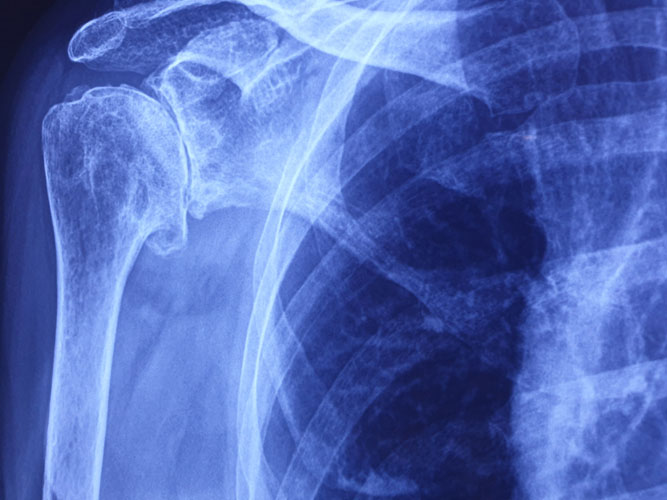

Pre Shoulder Replacement Surgery X-Ray for Arthritis